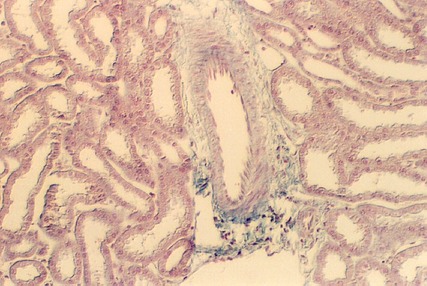

The above photograph is from Hematoxylin and Eosin stained kidney slide. Look at glomeruli in this slide and identify the capillaries, Bowman's capsule and Bowman's space. The afferent arteriole is the source of the capillaries in the Glomerulus. It is shown in this photograph, although the smooth muscle cells are difficult to see. The site where the arteriole enters the Renal corpuscle is called the "Vascular Pole". The opposite end is continuous with the proximal convoluted tubule. The above micrograph shows cells of the Proximal tubule beginning and joining with the cells of the Bowman's capsule (parietal epithelium). This is called the Urinary Pole. Find the vascular pole and the urinary pole on the above photo and following photographs. Also, find examples in your slide set.

The above photograph shows a higher magnification of the Urinary pole. It shows the transition between Bowman's Space in the Renal Corpuscle and the Proximal Convoluted tubule. Note that the cells show an abrupt transition from simple squamous to simple cuboidal in the proximal tubule (PT). Note also that the connective tissue elements supporting the tubules are stained bright blue in this Masson stained section.